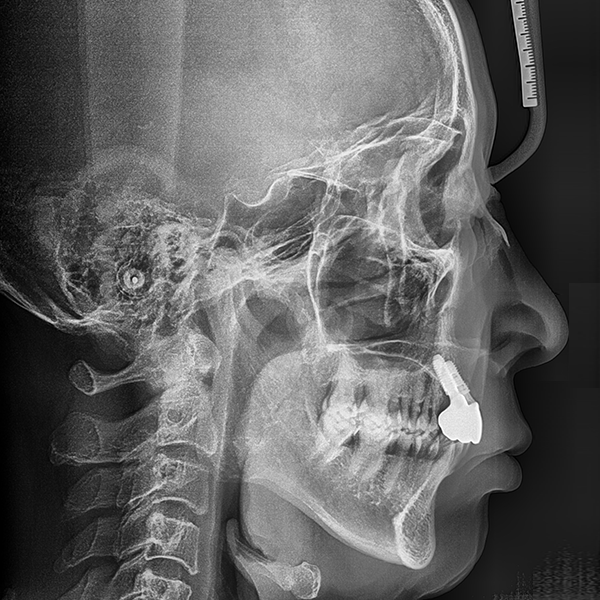

上顎/前歯部 / 3本以下 / 骨移植|高血圧

症例.110 60代 李*桂 2020-01-20 / 2020-3-21